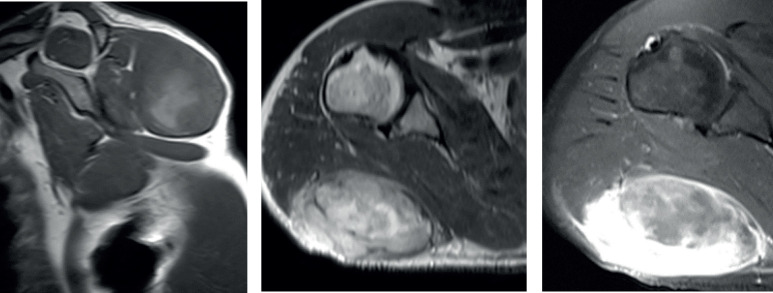

Objective: We report a case of Malignant Triton Tumor (MTT) arising in the right shoulder in a 46 year old male patient presented to our Musculoskeletal Oncology Clinic at Royal Rehabilitation center at King Hussein Medical Center during June 2018.

Case presentation: The patient was complaining of an 8 months long progressive right shoulder pain and swelling at the posterior lateral area of the shoulder. As accurate diagnosis is crucial in such case, investigations that included x-rays and magnetic resonance imaging (MRI) demonstrated an soft tissue tumor involving the right shoulder area leading to the differential diagnosis of aggressive soft tissue tumor which laid down the plan of an open incisional biopsy to be reported histopathological as a case of Malignant Triton Tumor which is a very rare and aggressive sarcoma originates from the peripheral nerve sheaths as it is subtype of malignant peripheral nerve sheath tumors after which excision of the entire tumor with safety margin was performed and referred for adjuvant chemotherapy.